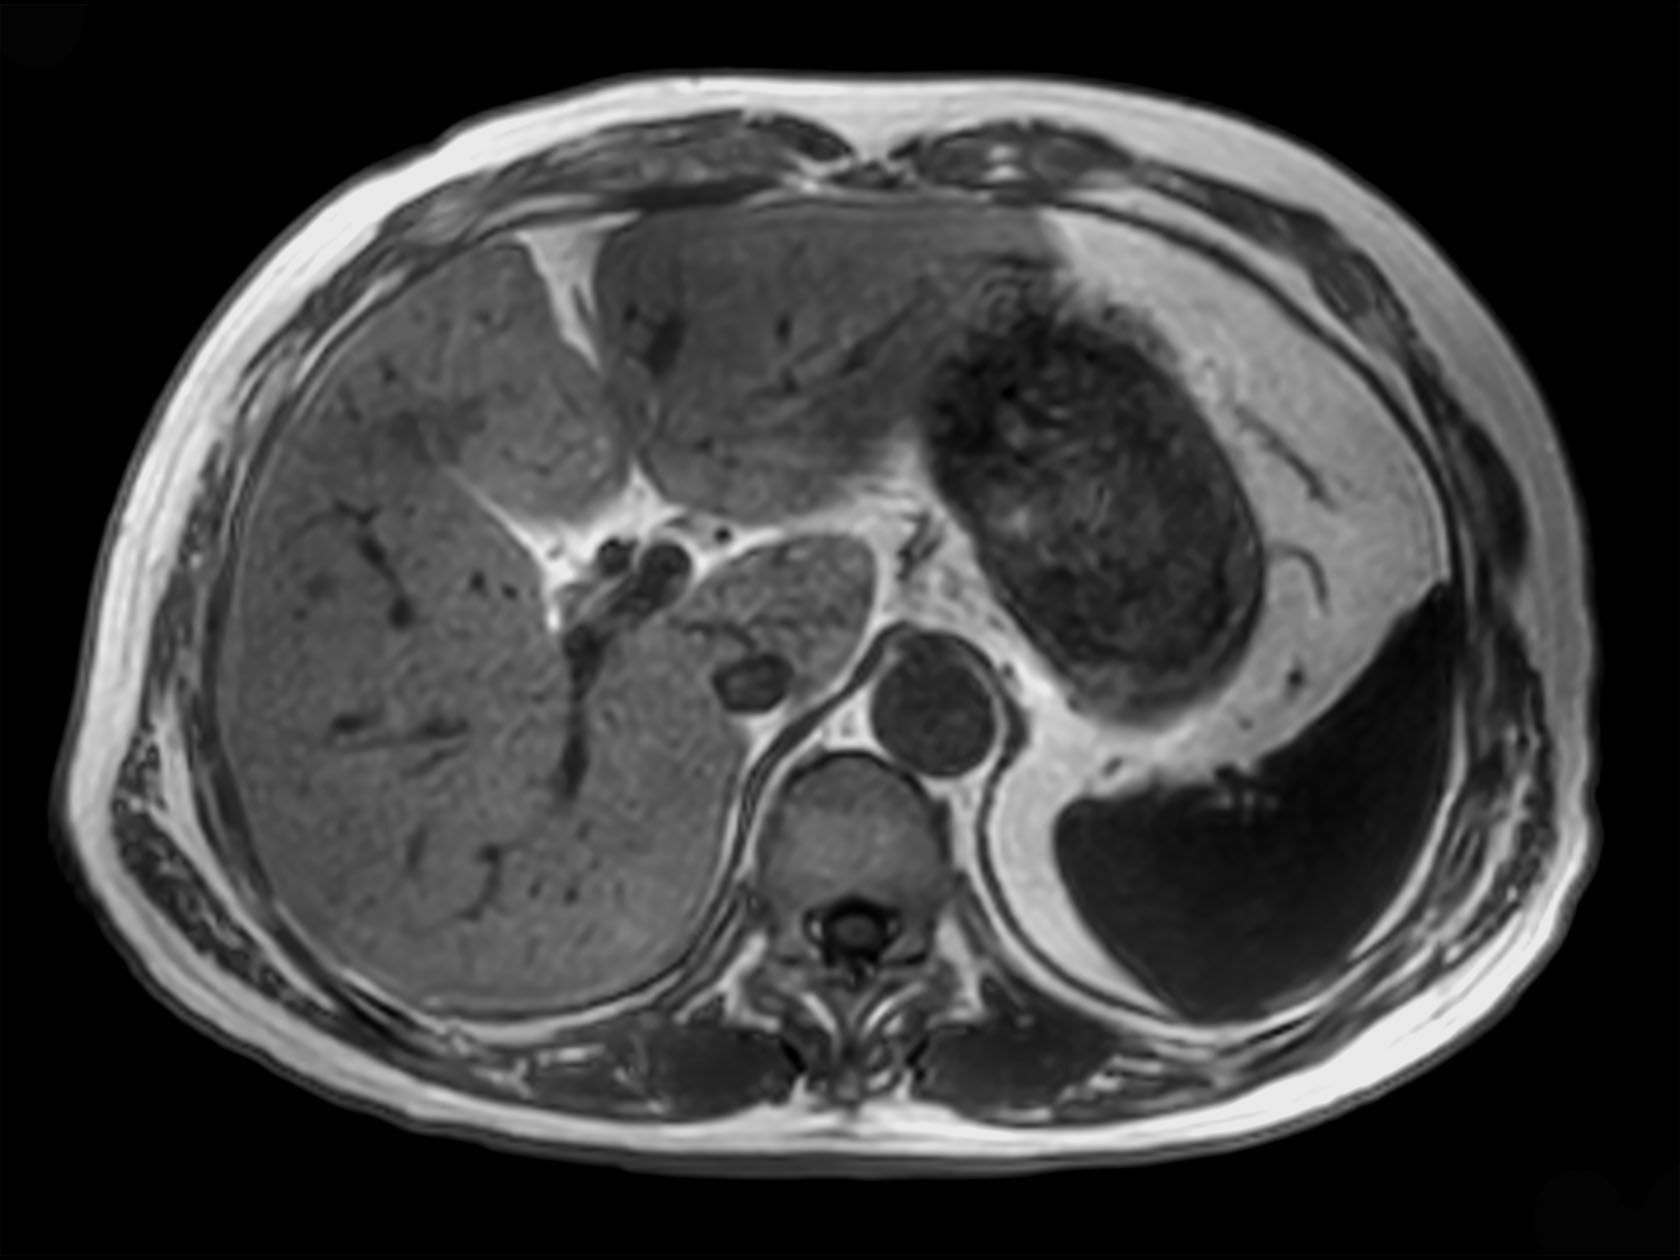

Axial mDIXON XD FFE (In Phase)